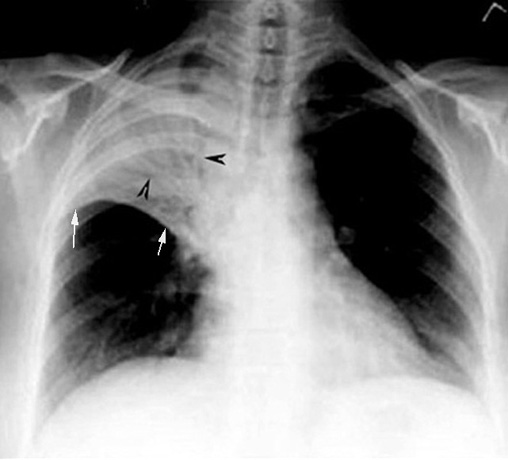

2. No significant loss of lung volume (White arrows pointing to transverse fissure)

- Alveoli are filled with inflammatory exudate, hence the volume of lung expands slightly and remains close to normal size even at the stage of resolution.

3. Air bronchogram

(Black arrowheads pointing to air bronchogram)

- Bronchi beyond 3-4 order of branching is not recognizable in CXR, because of loss of thickness and no contrast between intra bronchial air and surrounding alveoli containing air.

- In pneumonia the disease is primarily in the alveoli. Bronchi are patent. Air in the alveoli is replaced by inflammatory exudate. Now bronchi containing air is visible because of the contrast provided by liquid density induced by inflammatory exudate

White arrow points to minor fissure. Arrowheads: Air

in bronchi surrounded by filled alveoli - Air bronchogram. |